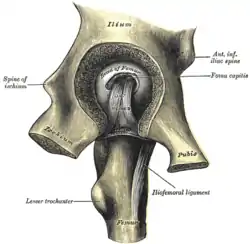

The cuplike acetabulum forms at the union of three pelvic bones — the ilium, pubis, and ischium.[6] The Y-shaped growth plate that separates them, the triradiate cartilage, is fused definitively at ages 14–16.[7] It is a special type of spheroidal or ball and socket joint where the roughly spherical femoral head is largely contained within the acetabulum and has an average radius of curvature of 2.5 cm.[8] The acetabulum grasps almost half the femoral ball, a grip deepened by a ring-shaped fibrocartilaginous lip, the acetabular labrum, which extends the joint beyond the equator.[6] The centre of the acetabulum (fovea) does not articulate to anything. Instead, it is lined with fat pad and attached to ligamentum teres. The acetabular labrum is horse-shoe shaped. Its inferior notch is bridged by transverse acetabular ligament.[5] The joint space between the femoral head and the superior acetabulum is normally between 2 and 7 mm.[9]

The extracapsular ligaments are the iliofemoral, ischiofemoral, and pubofemoral ligaments attached to the bones of the pelvis (the ilium, ischium, and pubis respectively). All three strengthen the capsule and prevent an excessive range of movement in the joint. Of these, the Y-shaped and twisted iliofemoral ligament is the strongest ligament in the human body. It has a tensile strength of 350 kg.[22] Iliofemoral ligament is a thickening of the anterior capsule extending from anterior inferior iliac spine to intertrochanteric line.[5] Ischiofemoral ligament is the thickening of posterior capsule of the hip and pubofemoral ligament is the thickening of the inferior capsule.[5] In the upright position, iliofemoral ligament prevents the trunk from falling backward without the need for muscular activity, thus preventing excessive hyperextension. In the sitting position, it becomes relaxed, thus permitting the pelvis to tilt backward into its sitting position. Ischiofemoral prevents excessive extension and the pubofemoral ligament prevents excess abduction and extension.[24]

The intracapsular ligament, the ligamentum teres, is attached to a depression in the acetabulum (the acetabular notch) and a depression on the femoral head (the fovea of the head). It is only stretched when the hip is dislocated, and may then prevent further displacement.[22] It is not that important as a ligament but can often be vitally important as a conduit of a small artery to the head of the femur, that is, the foveal artery.[26] This artery is not present in everyone but can become the only blood supply to the bone in the head of the femur when the neck of the femur is fractured or disrupted by injury in childhood.[27]

Hip joint. Lateral view.

Hip joint. Lateral view. Hip joint. Lateral view.